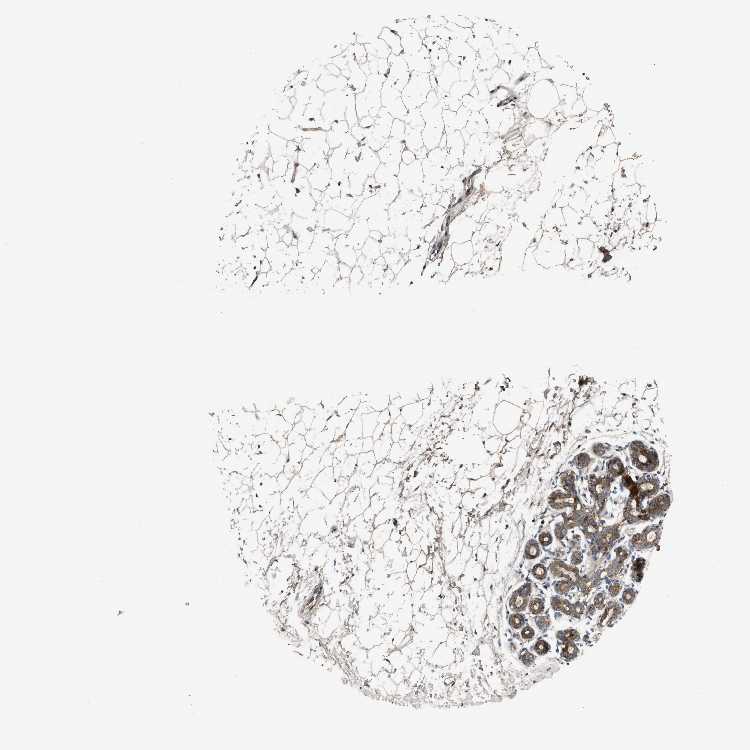

ZNF70